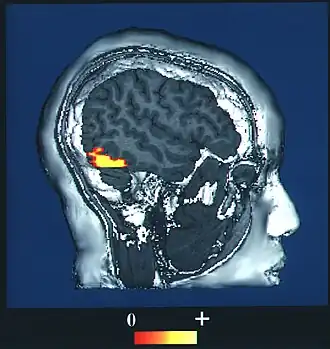

De cognitieve neurowetenschap is erin geslaagd toetsbare verklaringsmodellen op te stellen van de 'neurale correlaten van bewustzijn': het wetenschappelijk aantoonbare verband tussen neurologische activiteit in de hersenen en het bewustzijn.[4]

De uitdaging binnen de cognitieve neurowetenschap is de neurale correlaten van bewustzijn te verklaren als een oorzakelijk verband.